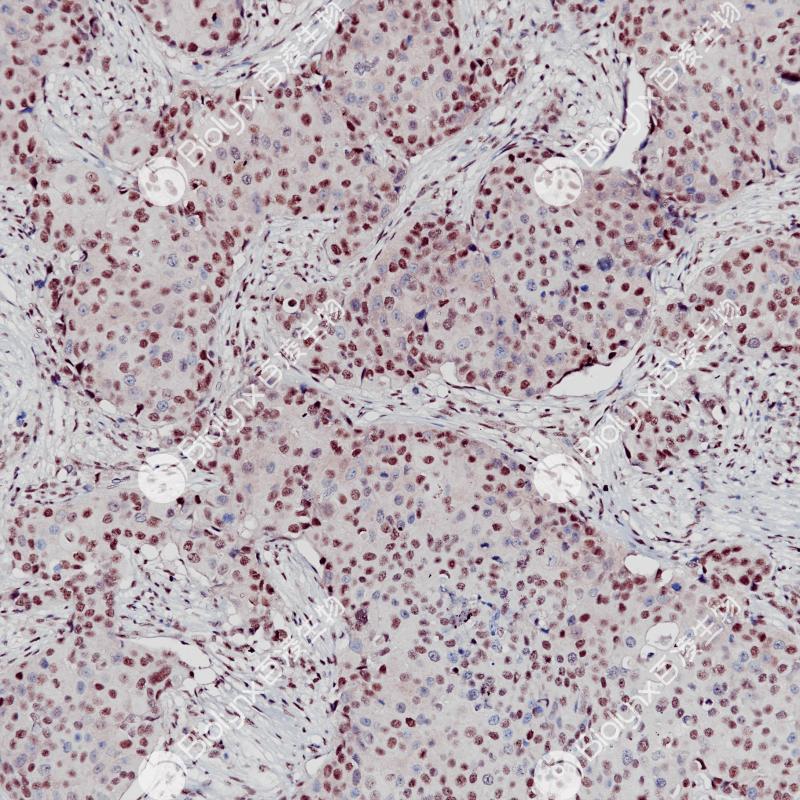

乳腺癌E2F4(BP6256)染色

E2F4是E2F家族中的一种转录因子蛋白,由16号染色体上的E2F4基因编码。E2F家族在控制细胞周期和肿瘤抑制蛋白的作用中起着至关重要的作用,也是小DNA肿瘤病毒转化蛋白的靶点。E2F4在多种肿瘤组织中表达,如乳腺癌、子宫内膜癌、结肠癌等。

亚细胞定位

细胞核